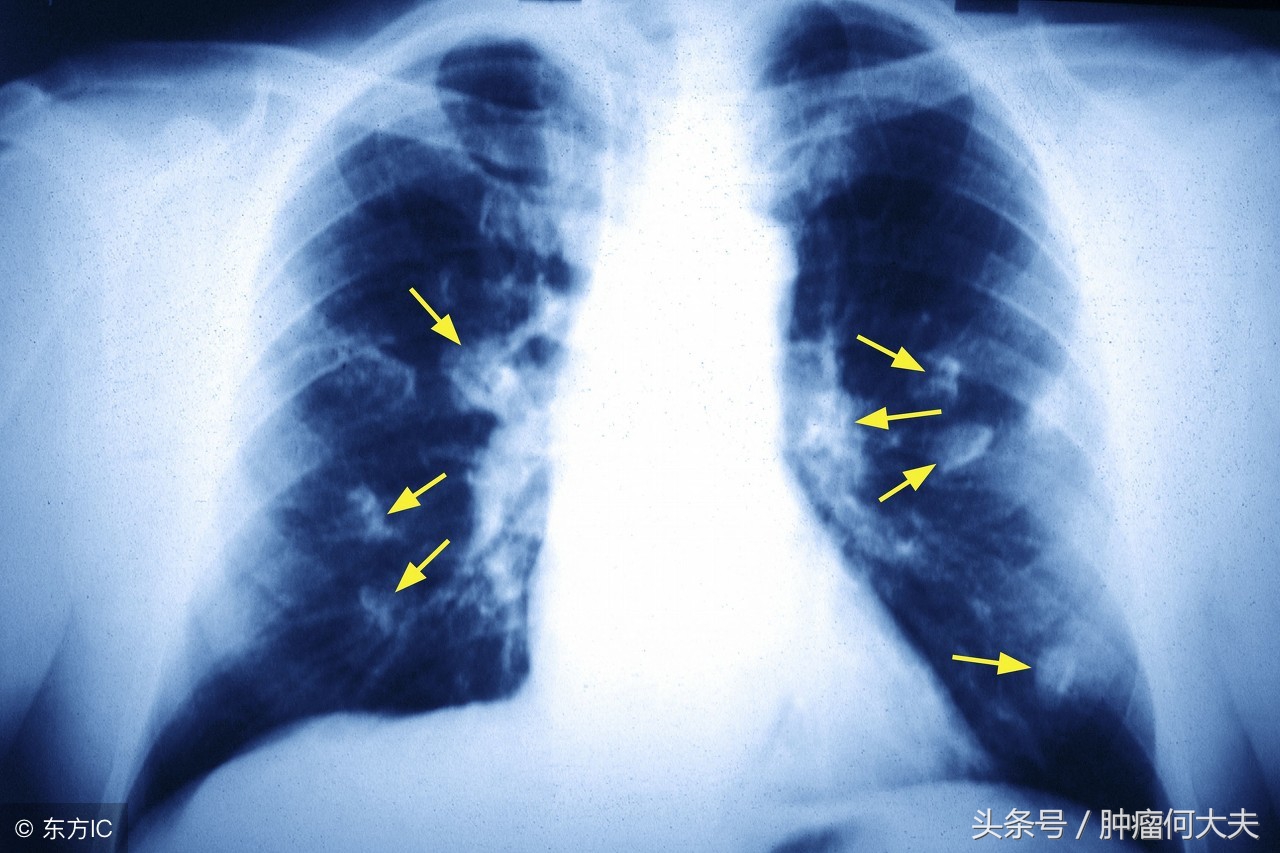

肺癌筛查

研究结果显示,无论使用何种检测方法,在训练集中均检测到41%(29%至54%)的早期肺癌,定义为I至IIIA期。测试集中,检测到50%(29%至71%)的早期肺癌。对于晚期肺癌,定义为IIIB至IV期,测定结果表现较好,90%的病例在测试中得到验证。